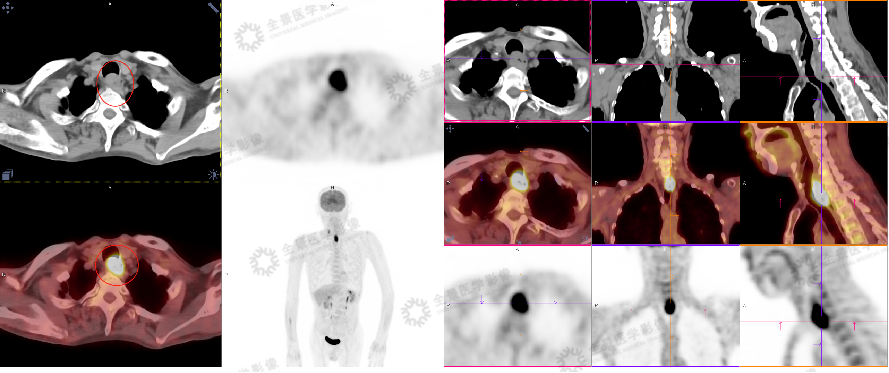

发现王先生的食管异常后,消化内镜中心迅速与影像科联动。影像科即刻响应,为王先生紧急开通院内绿色通道。11 点 34 分,王先生顺利接受 PET/CT 全身扫描。

影像所见:食管颈段及胸上段(C6 - T1 椎体层面)管壁增厚,FDG 代谢异常增高,高度怀疑为食管癌且侵犯气管后壁,同时检测到右侧颈深下间隙淋巴结转移。

12 点 20 分,PET/CT 影像诊断报告初步出具,影像科与佲医荟消化内科专家联合报告解读,结合胃镜和 PET/CT 的检查结果,对王先生的病情进行综合分析,根据病情和病患情况,协助其后续就医治疗。

影像科 PET/CT 基于其全身性和功能性优势,进一步明确病变性质、侵犯范围以及是否存在转移,同时补充了身体其他部位健康信息,为后续治疗方案的制定,提供了不可或缺的依据;